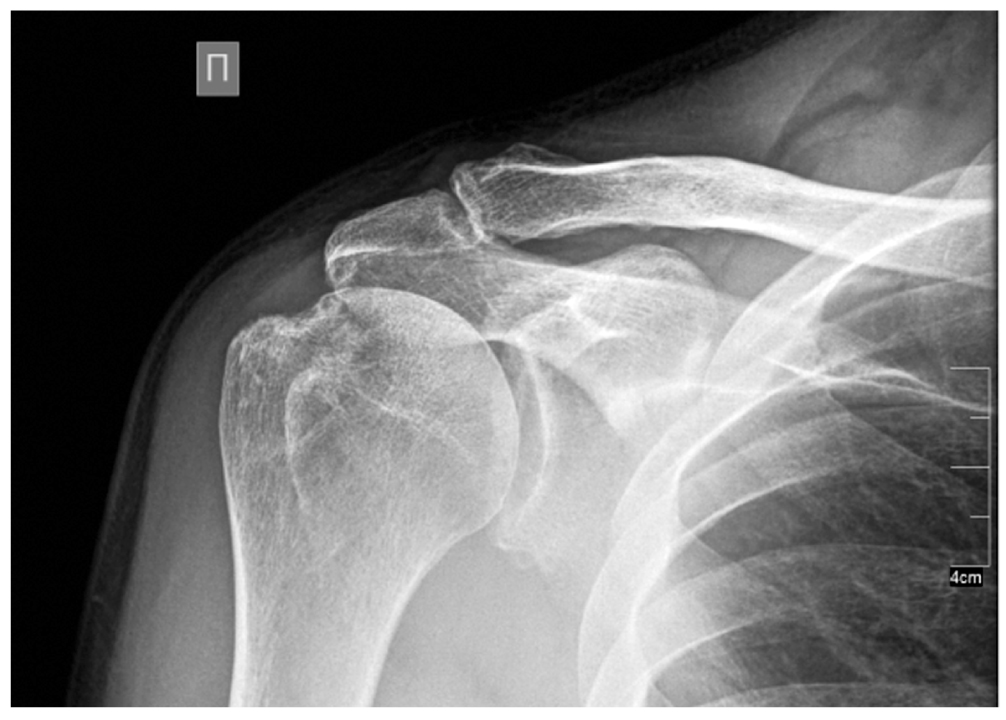

По данным рентгенографии правого плечевого сустава: остеоартроз правого плечевого сустава, ключично-акромиального сустава II степени (рис. 2). Остеопороз.

Рис. 2. Рентгенография правого плечевого сустава.

Fig. 2. X-ray of the right shoulder joint.